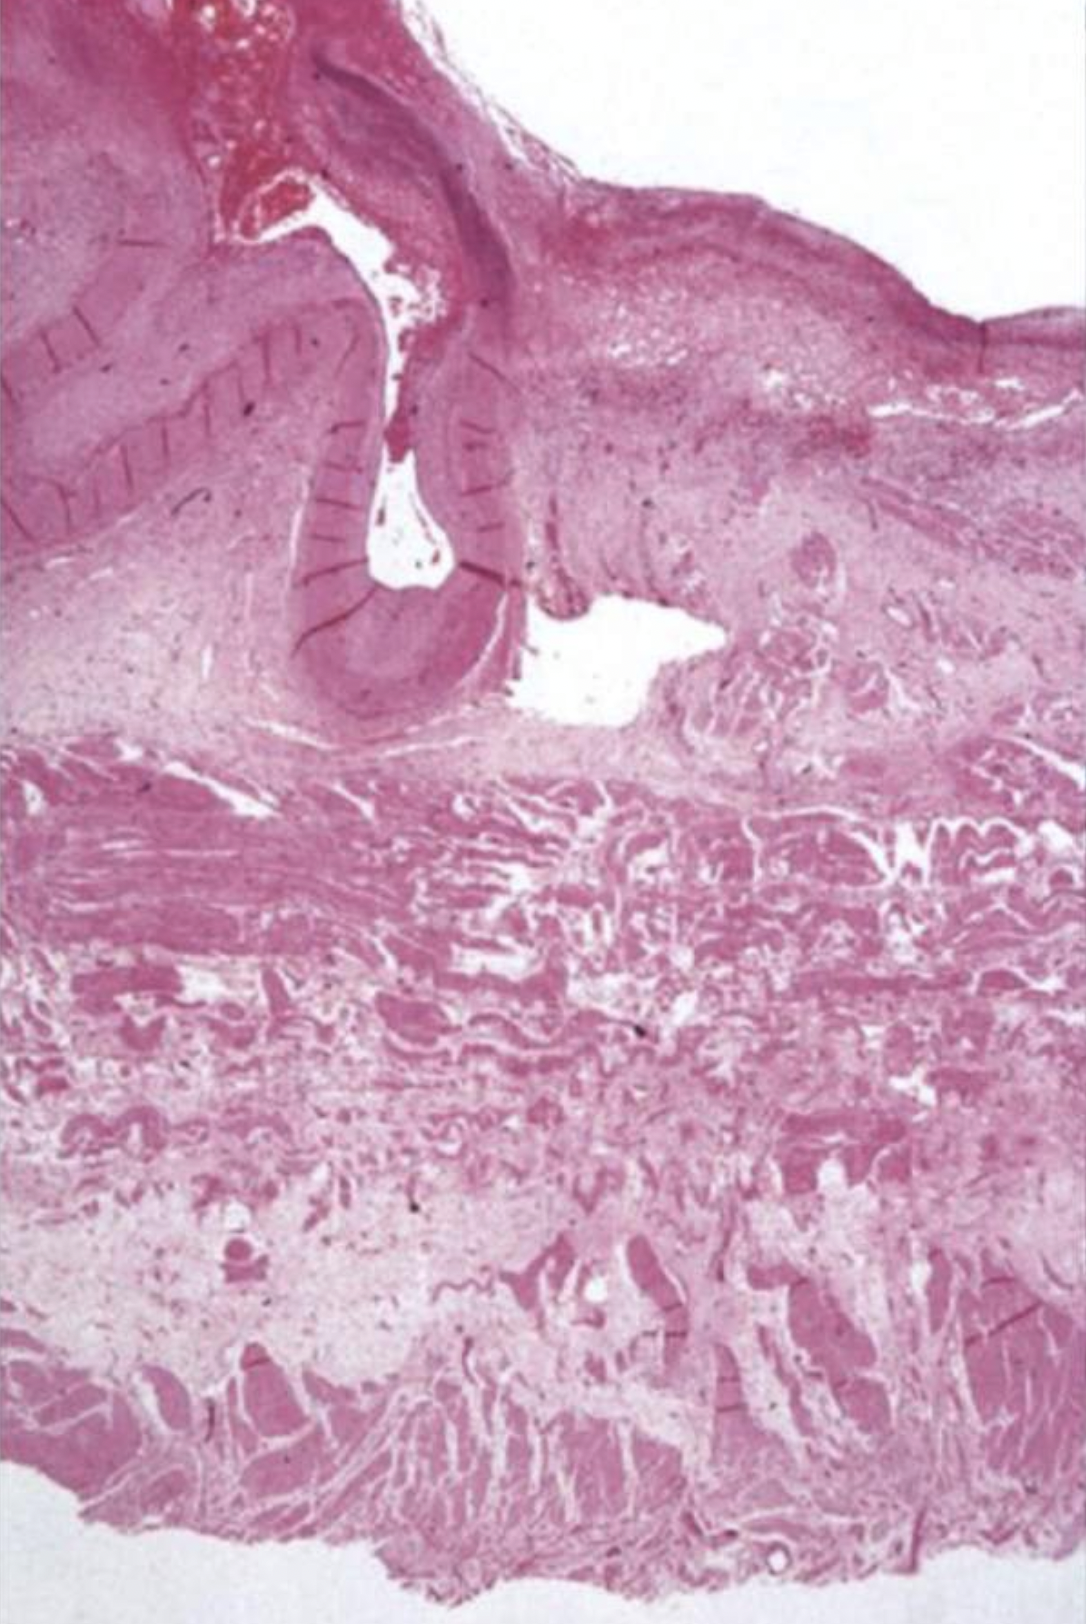

Describe what you can see in the histological images- where in the lesion does this tissue section come from?

Loss of glandular tissue on LHS

Inflammation causes hyperplastic inflammation to local tissues

What can you see in this image?

Looks like a ruptured artery-which may explain vomit

Completely ulcerated mucosa

Loss of muscularis layer